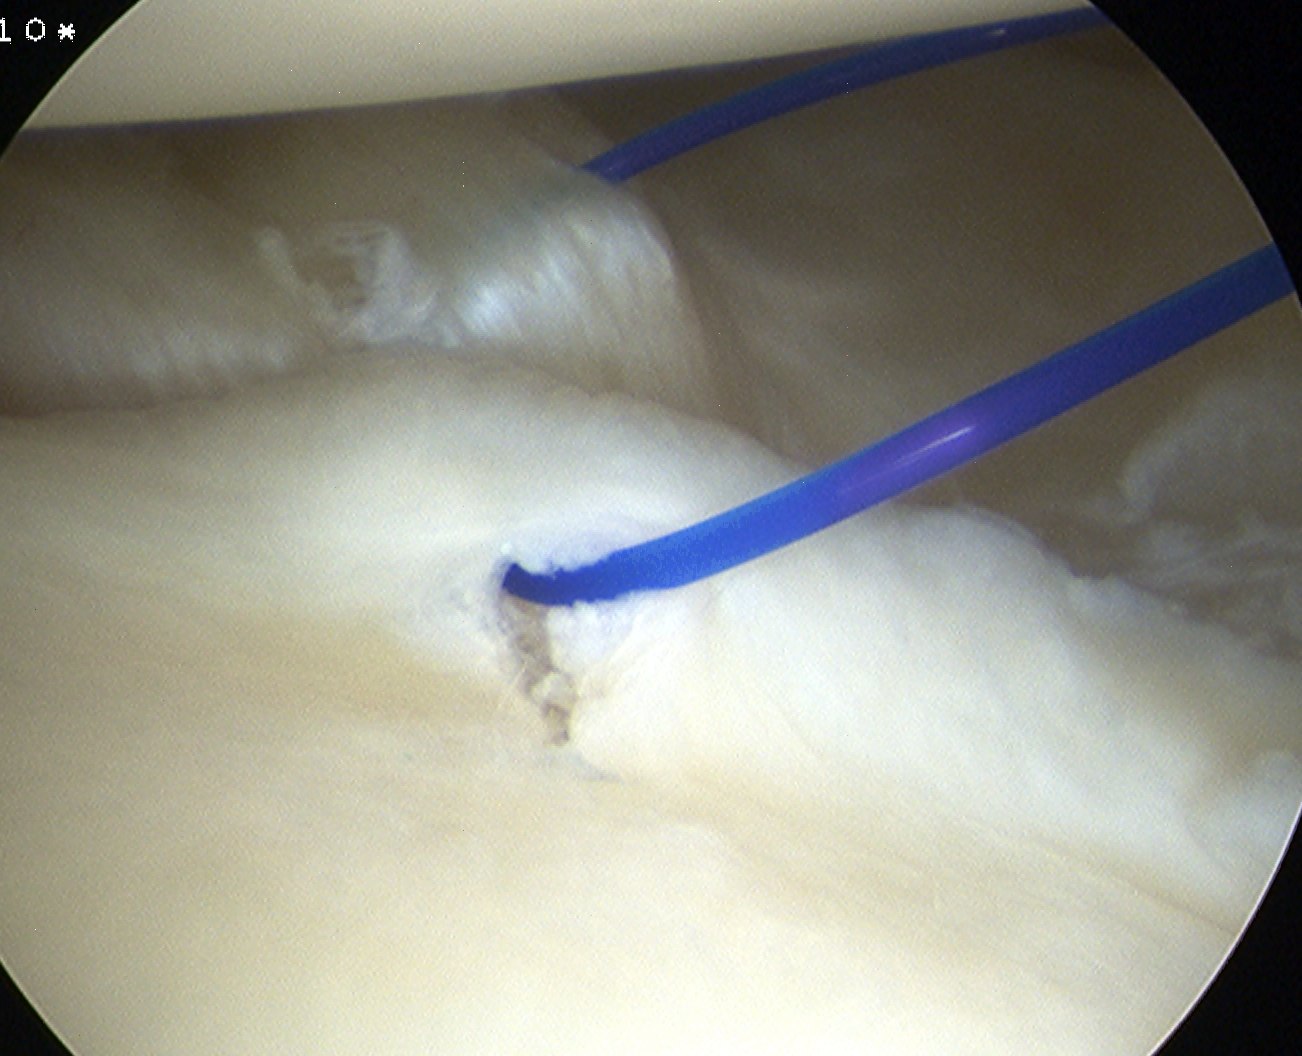

Anterior capsular plication with sutures

Anterior capsular plication +/- rotator interval closure

- option 1: Suture plicate capsule to labrum

- option 2: Anchors in glenoid and use to plicate capsule to labrum